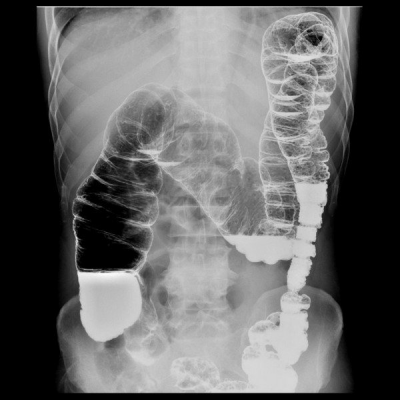

Диагностика дуоденита осуществляется в ходе гастроскопии — погружения эндоскопического зонда в желудок и кишечник пациента. В качестве дополнительных способов подтверждения диагноза применяются:

- рентгенографическое исследование желудочно-кишечного тракта;